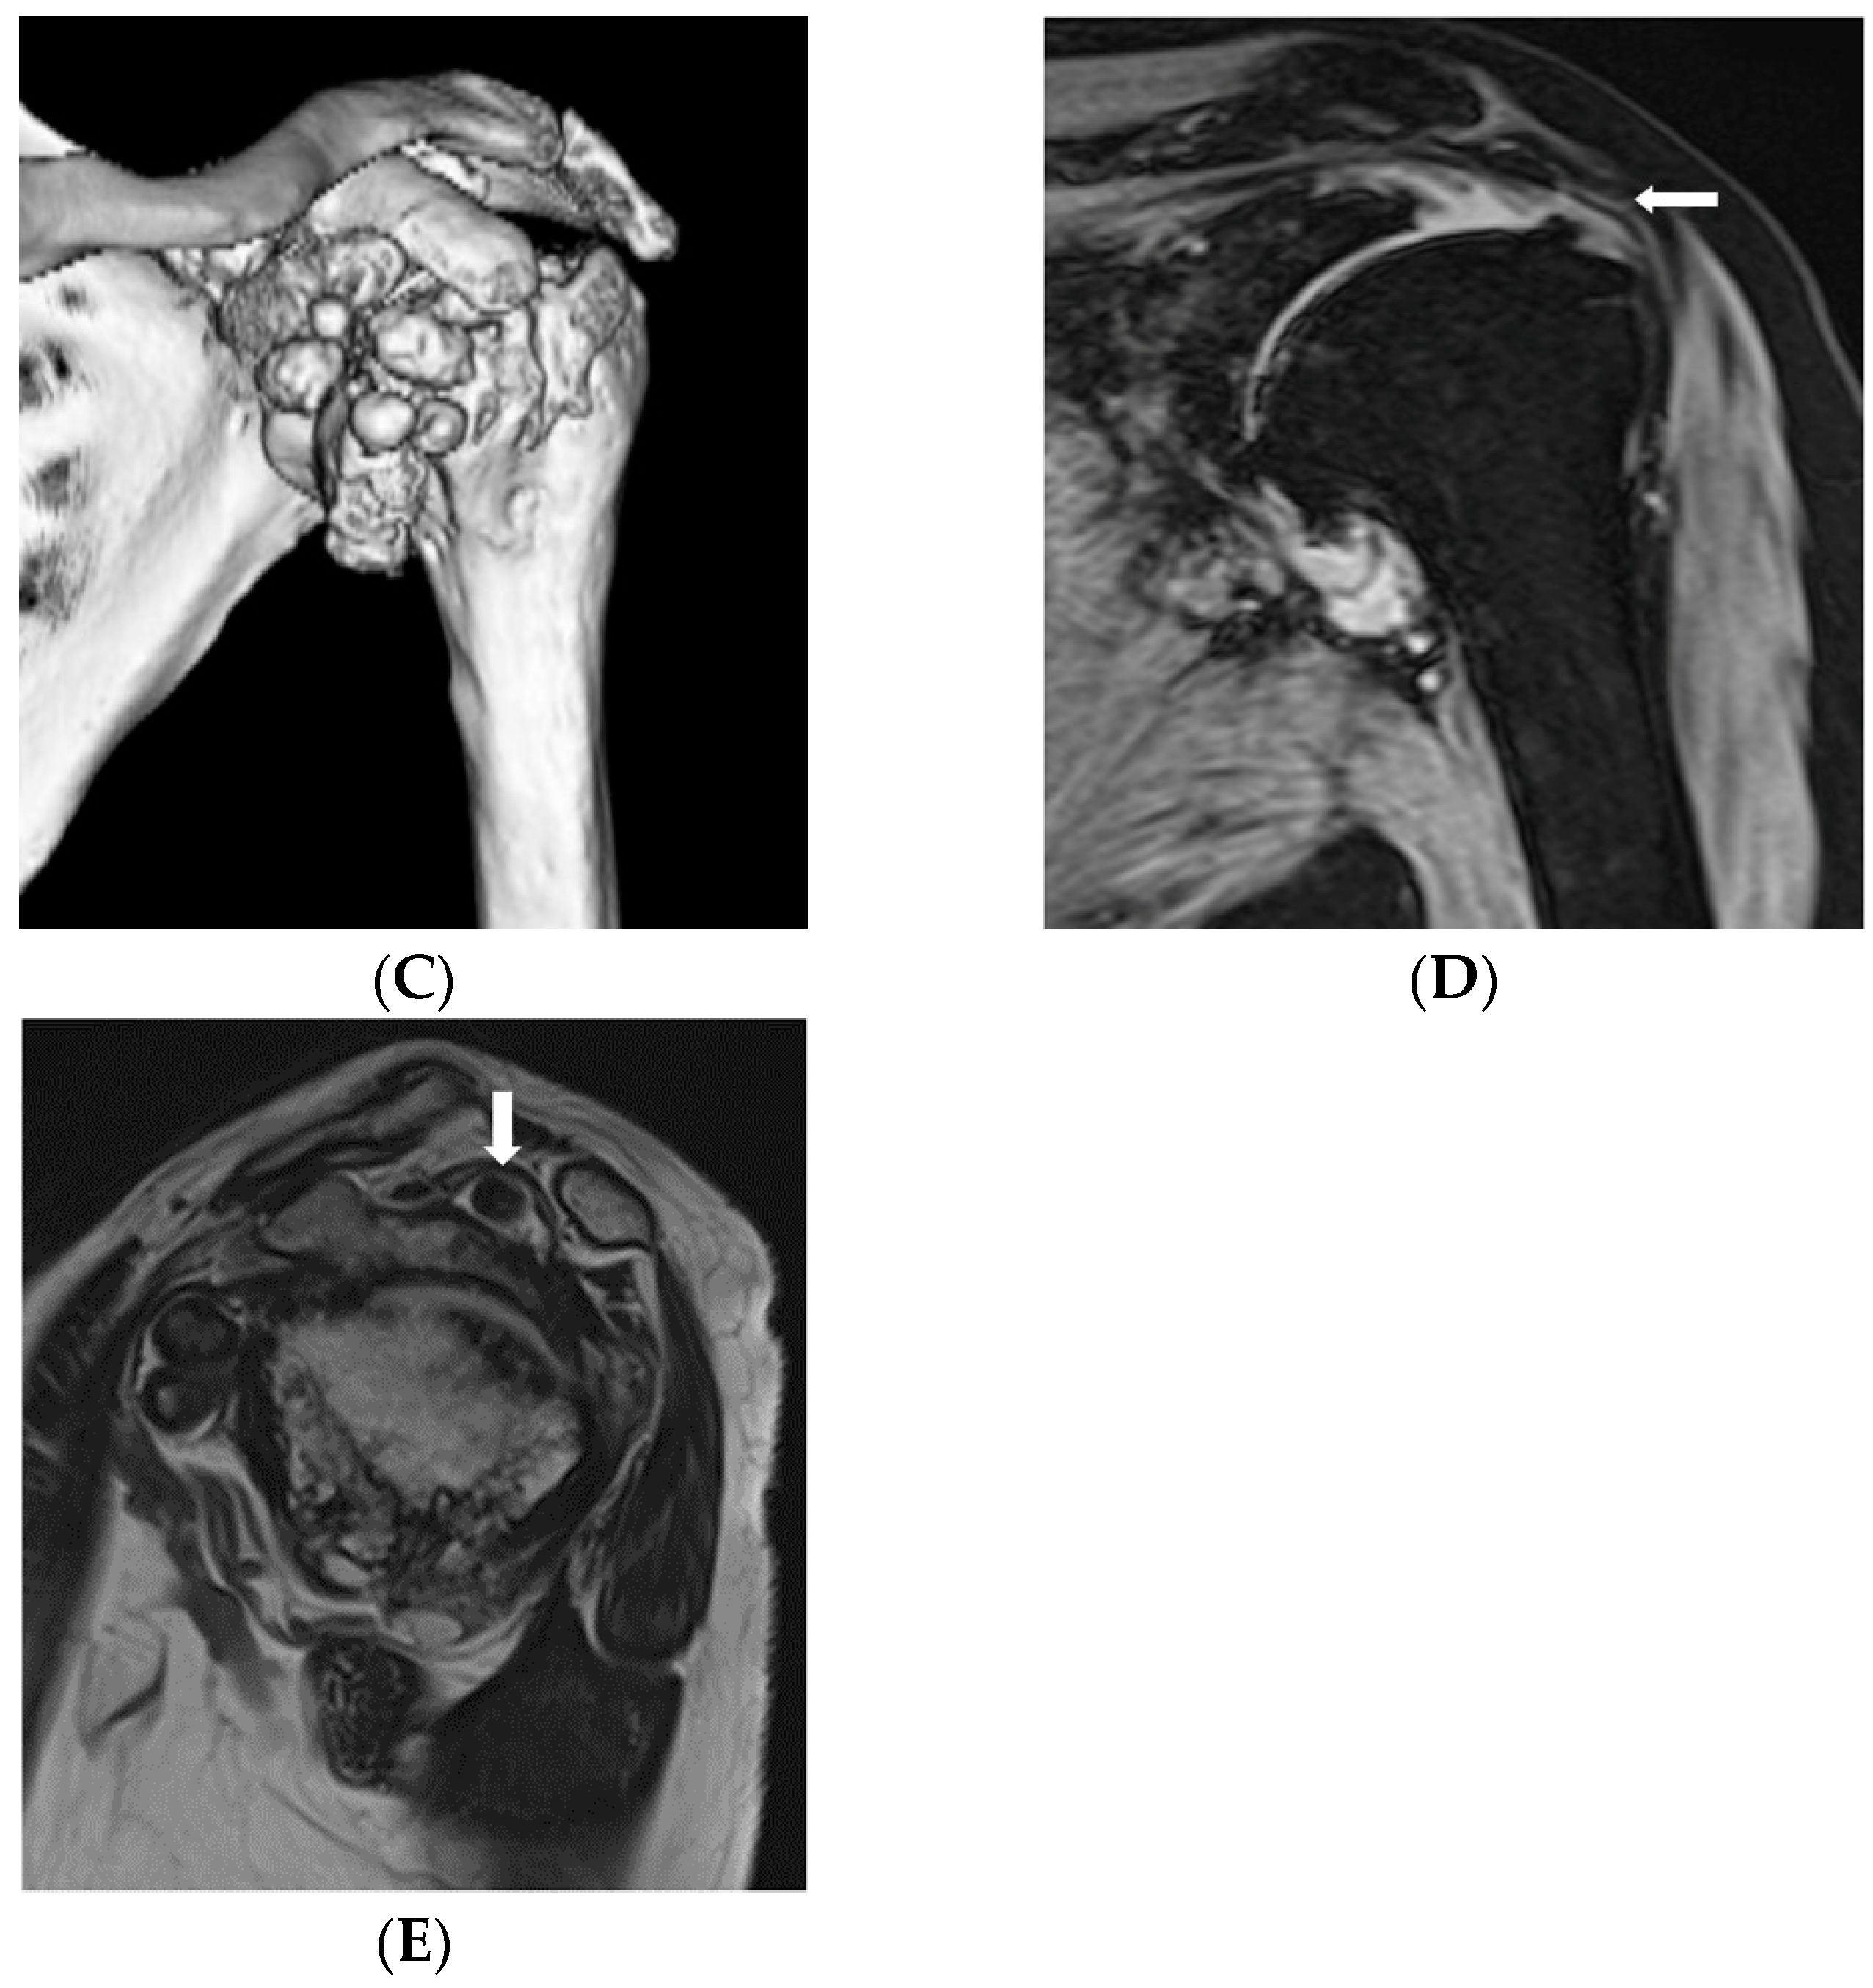

2.4. Histopathological Examination

The loose body was found to consist of a cartilage component and bone tissue with hyalinization (Figure 2). No findings indicative of malignancy were evident, and since nodular cartilage arrangement was found, primary osteochondroma was diagnosed. Synovial osteochondromatosis could be diagnosed.

Figure 2.

Postoperative evaluation. (A) Postoperative X-ray. After reverse shoulder arthroplasty, the mass in the shoulder joint has disappeared, and the course is favorable; Pathologic findings. (B) On a cut surface, the surface was covered with whitish cartilage, while the center consisted of yellowish bone tissue. (C) The histological picture showed a nodular mass covered with hyaline cartilage. In the center of the cartilage, ossification was present. No findings of malignancy were seen. Lammification structure of the hypertrophic chondrocyte was observed on the surface of the lesion, which led to the diagnosis of primary osteochondroma.